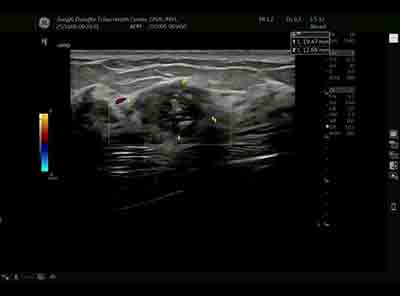

血流模式的精細評估 乳腺良惡性腫瘤的血流特征存在顯著差異。E11采用的超微細血流成像技術(shù)具有突破性意義:

準(zhǔn)確區(qū)分腫瘤邊緣與內(nèi)部血流分布 惡性腫塊通常表現(xiàn)為血流豐富、走行紊亂、動靜脈瘺形成,而良性病變血流相對稀疏、走行規(guī)則。這種差異為鑒別診斷提供了重要參考。